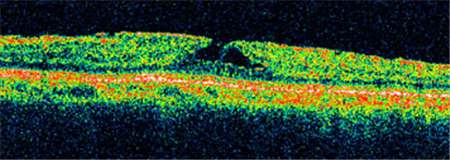

?、衿邳S斑裂孔通常無需手術(shù),若裂孔惡化至Ⅱ-Ⅳ期就需要考慮進(jìn)行手術(shù)治療。上海眼科醫(yī)院排名通過學(xué)相干斷層掃描來診斷黃斑裂孔,可清楚照出玻璃體及視網(wǎng)膜的情況,了解患者黃斑裂孔的大小、位置等。